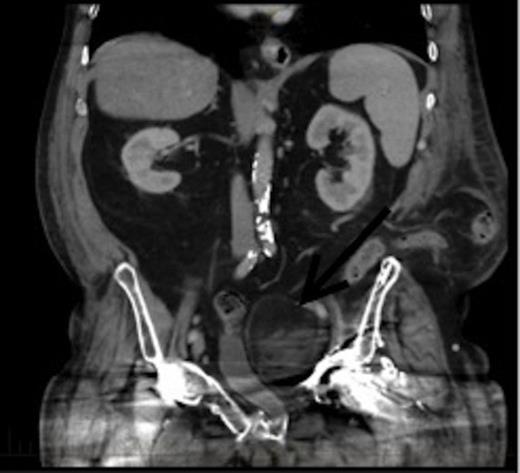

An axial section of the CT demonstrating a 6.7x6cm.3x7.3cm left pelvic lesion adjacent to the trauma site. Arrow denotes the EMH lesion

A CT scan demonstrated a 6.7x6.3cmx7.3cm well-defined left pelvic mass immediately medial and adjacent to the left acetabulum compressing the bladder and the iliac vessels. The mass was heterogeneous in density comprising of both muscle and fat with no calcifications. He underwent a repeat staging-CT, MRI, whole body thallium scan, and a CT-guided biopsy. The MRI scan confirmed a lobulated well-circumscribed mass with a heterogeneous T1 and T2 appearance. Areas of hyperintensity reported on CT corresponded to fatty components within the mass, while the rest of the mass appeared relatively hypointense to skeletal muscle, and was thought to be consistent with a liposarcoma. The Single Photon Emission Computed Tomography (SPECT) scan demonstrated low-grade activity in the mass and the staging-CT did not reveal any signs of malignancy. A confirmatory CT-guided biopsy however diagnosed the mass as EMH tissue, while a CT angiogram demonstrated no external compression of the iliac vessels.

CT coronal view of the lesion demonstrating compression of the bladder. Arrow denotes the EMH lesion

This patient was subsequently discussed at a multidisciplinary meeting, where it was decided that in view of the urinary symptoms and his high operative risk, the mass should be treated with CT-guided radiofrequency ablation using a multi-lined electrode. However, the patient declined treatment and was temporarily lost to follow up after moving interstate. Two years later, he presented to the hospital with bowel obstruction secondary to an incisional lumbar hernia, and the follow up CT scan (Figures 2 and 3) revealed no increase in the size of the mass, and repeat biopsy re-confirmed the presence of EMH. His urinary symptoms remained stable.